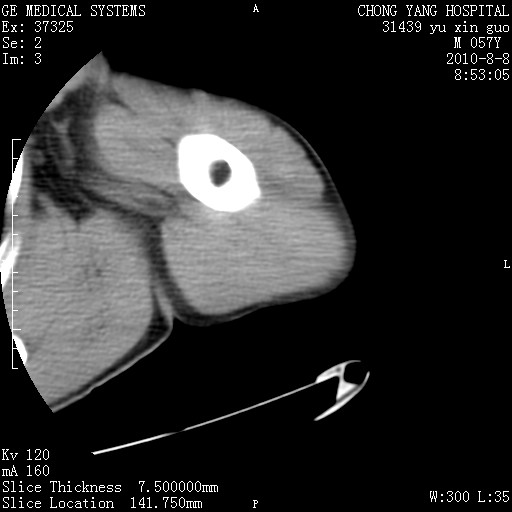

标题: CT28267:M57Y 上臂包块8年余。 [打印本页]

标题: CT28267:M57Y 上臂包块8年余。

典型脂肪瘤改变

包膜光滑、完整的脂肪密度肿块,支持脂肪瘤。

脂肪瘤。有ct值?